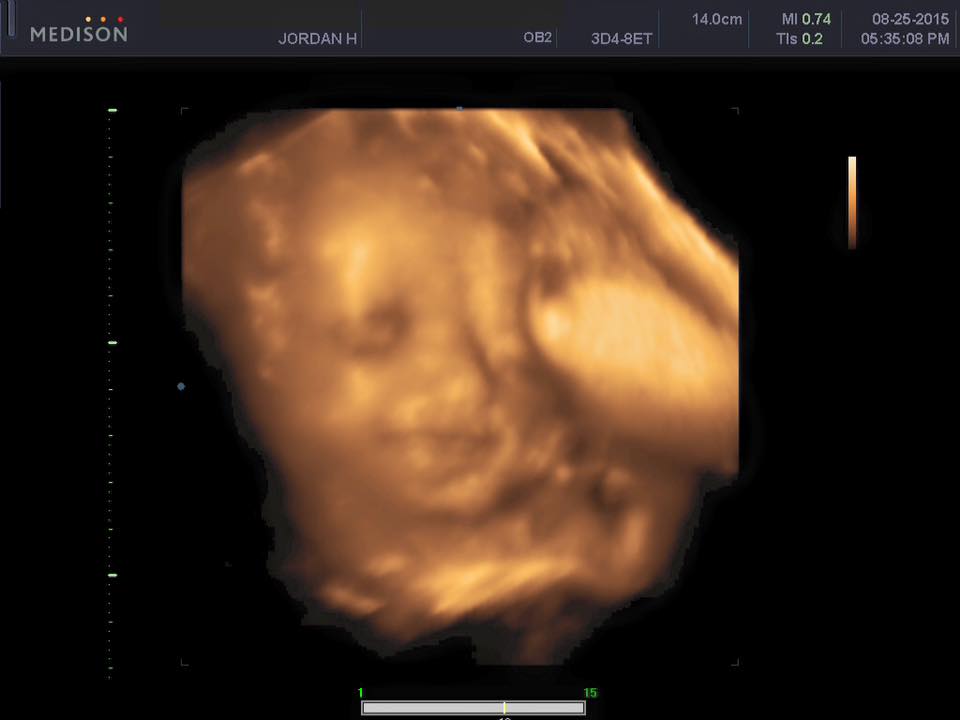

Baby Facts: We had our 3D/4D ultrasound this week. IT WAS AMAZING! Worth every penny. We confirmed baby is in no doubt A GIRL! (Good thing too…I didn’t want to return all the pink). We also got to see her adorable little face, which made me tear up a little bit. It amazes me how the body turns something so tiny into a little human in just 40 weeks.

Anyways, baby has some chubby cheeks already, as you can see. She also is already facing the correct way for her arrival into the world. The funniest moment is seeing how tight she is getting in there, our little goof was getting a bit too close to my belly and ended up squashing her nose a couple of times. (lol)